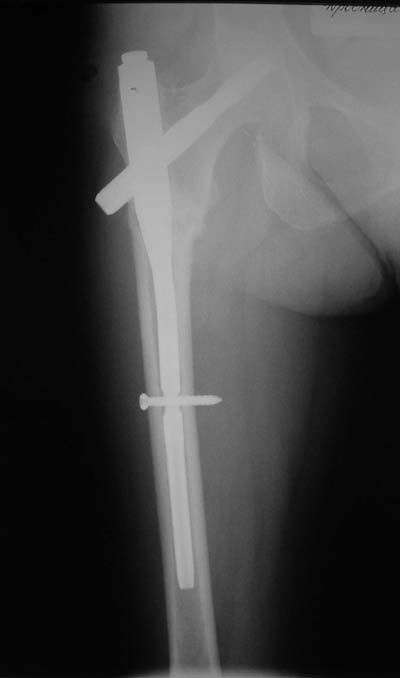

Да? Качество рентгенограмм конечно неочень, но ведь это нестабильный перелом 31.А2.2, не так ли?

Не думаю так. см вложение.